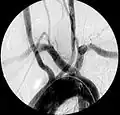

| Aberrant subclavian artery on MR angiography. | |

Aberrant right subclavian artery at angiography.